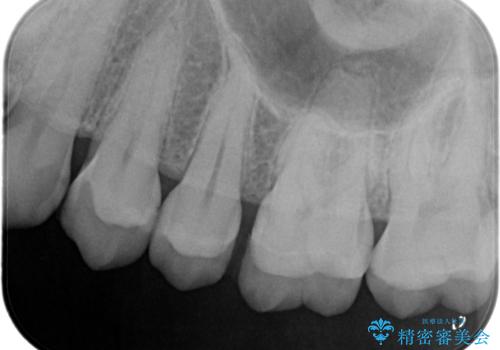

- 前医で治療された詰め物の部分に、定期検診で虫歯が見つかったため、セラミックインレーにて修復治療を行いました。

接着時にはラバーダム防湿を行っています。